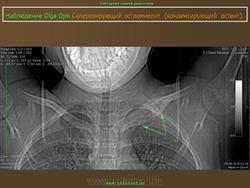

Склерозирующий остеомиелит из ключицы впервые был описан как заболевание лица в 1974 году. Существует боли и часто локализуется опухоль из медиальной трети ключицы, с повышенной плотностью радио.Sternoclavicular совместных, как правило, никогда не занимался. Он также известен как асептический расширения остеосклероз из медиального конца ключицы.

Множественные мелкие и крупные (до 10 мм) очаги остеосклероза округлой или овальной формы, расположенные в эпифизах трубчатых костей, а также в других костях, за исключением ключицы.